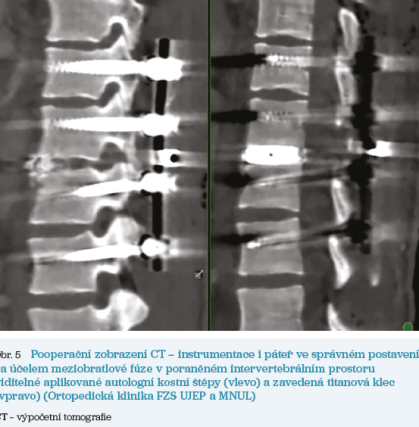

Provedení meziobratlové fúze je základní metodou k prevenci budoucího vzniku poúrazové deformity, nestability či selhání instrumentace a dosažené repozice. Kostního srůstu sousedních obratlů dosahujeme provedením resekce meziobratlového disku a aplikací autologního či alogenního kostního materiálu do meziobratlového prostoru za účelem kostního srůstu. Alternativou jsou arteficiální kostní náhrady nejčastěji na bázi kalciumfosfátu, biokeramiky či bioaktivního skla. Za účelem udržení rozestupu obratlů do vytvoření srůstů bývají aplikovány také meziobratlové klece. Klece jsou nejčastěji titanové, z polyetherketonových vláken (PEEK) či karbonové.

Operačních přístupů k páteři je v zásadě několik, v rámci primárního ošetření je nejčastější zadní přístup.Ze zadního přístupu zavádíme pedikulární šrouby, stabilizujeme, provádíme repozici, dekompresi, je možné i současné provedení meziobratlové fúze (obr. 2, 3, 4, 5). Vytvoření meziobratlové fúze bývá častěji prováděno až při přední operaci ve druhé době, většinou z předního či bočního přístupu k páteři. Vytvoření intervertebrální fúze, tedy kostního srůstu obratlových těl, je ze zadního přístupu sice možné (transpedikulárně či transforaminálně), ale může být technicky složitější, jelikož se musíme vyhýbat nervovým strukturám – míše a míšním kořenům. Nezanedbatelnou komplikací při proniknutí do páteřního kanálu je jizvení, které může být následnou příčinou chronických neurologických kořenových projevů – parestezie, iritační bolesti. Tento stav způsobuje tzv. failed back surgery syndrom (FBSS) a má jen velmi omezené možnosti další léčby. Proto je v dnešní době standardem dvoudobé ošetření poranění páteře, přičemž druhá operace slouží k vytvoření kostní fúze v oblasti předního sloupce páteře samostatným přístupem.

Obr. 5 Pooperační zobrazení CTPřední přístupy k páteři se liší podle úrovně a úseku páteře. V oblasti krční páteře je přední přístup daleko šetrnější než přístup zadní. V oblasti hrudní páteře je prováděn cestou thorakotomie, kdy mezi žebry pronikáme do pleurální dutiny a po kolapsu stejnostranné plíce při selektivní ventilaci pohodlně přistupujeme k hrudní páteři. V oblasti L2–L3 je nutno provést lumbotomii z boku retroperitoneálním prostorem, v úseku L4–L5 je možno postupovat přístupem retroperitoneálním, např. pararektálním řezem, či přístupem transperitoneálním, např. Pfannenstielovým řezem, s nutností respektování magistrálních cévních struktur.